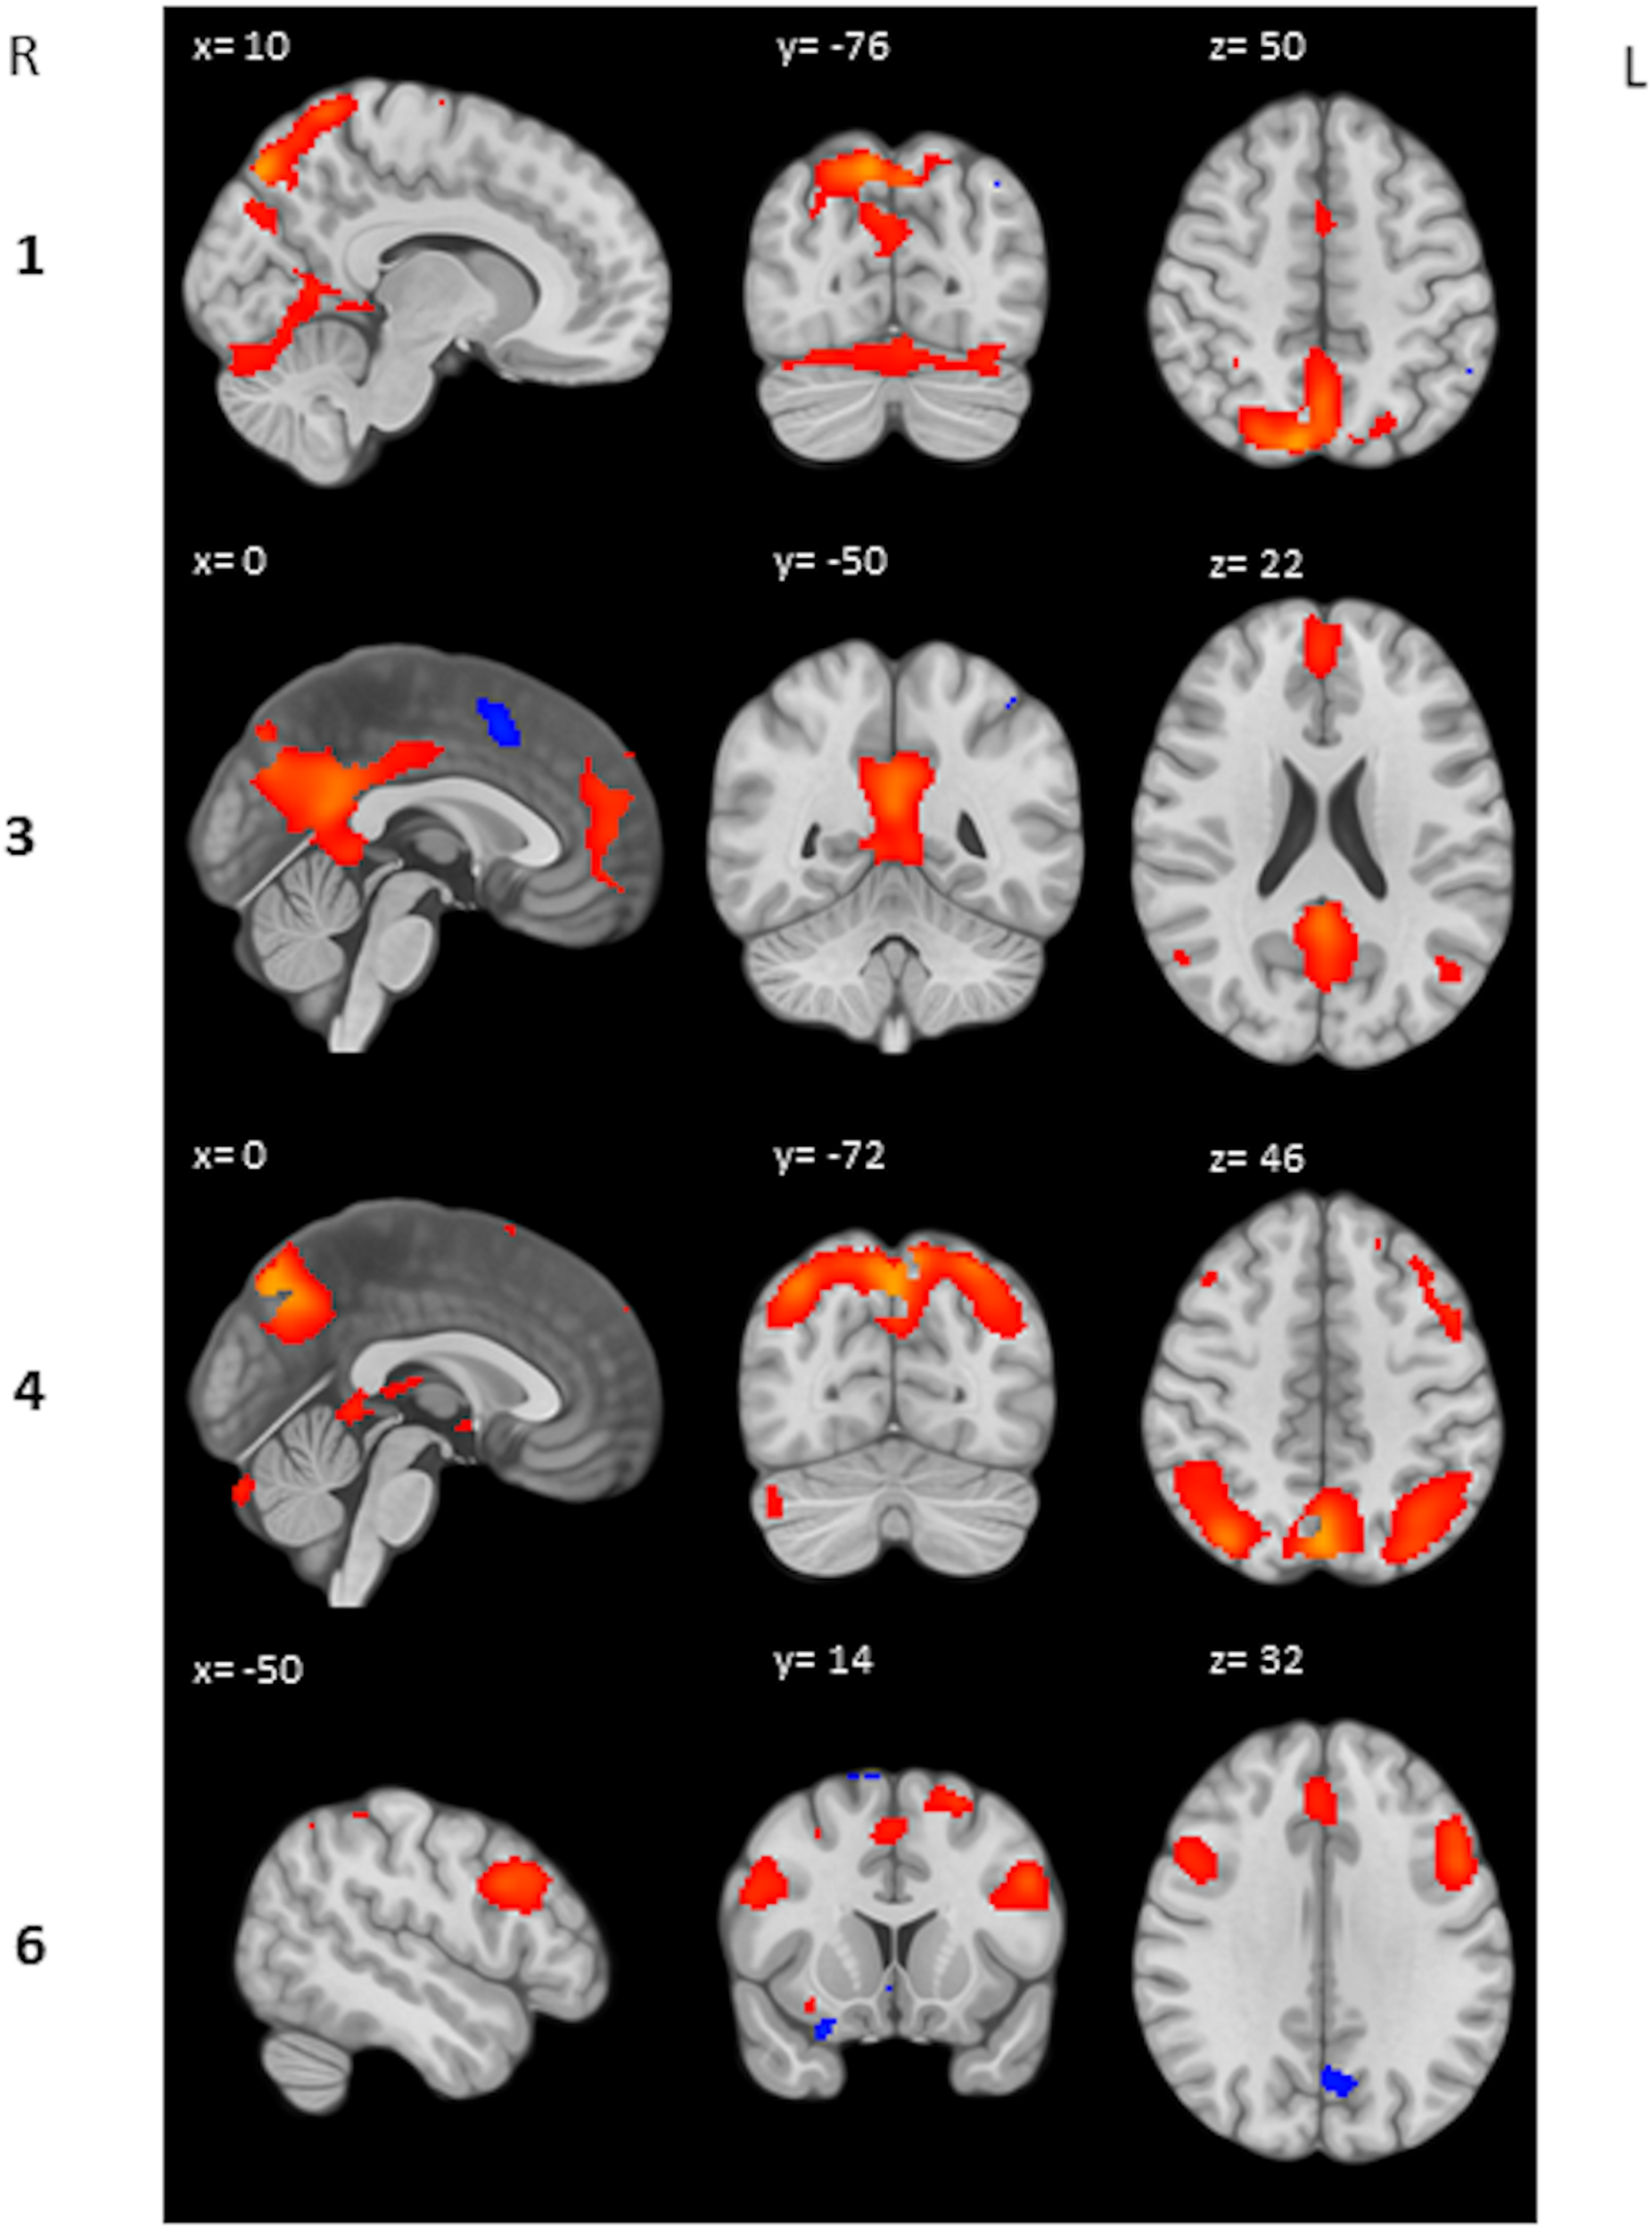

Coactivated Brain Regions Within the Heartbreak Group

We performed a post hoc feature-based ICA on the 2-back > 0-back contrast images of the heartbreak group. Six IC’s were estimated and visually inspected. IC 2 and IC 5 were considered noise and therefore not included in further analyses. IC 1 represents among other brain regions the precuneus, anterior cingulate gyrus and supplementary motor cortex. IC 3 represents the posterior cingulate gyrus and paracingulate gyrus. IC 4 represents the precuneus and the lateral occipital cortex superior division. IC 6 represents among others the middle frontal gyrus and paracingulate gyrus. Table 5 shows peak coordinates and corresponding Z-scores for the remaining four IC’s. Figure 2 displays the peak activation for the four IC’s.

TABLE 5

| IC | Brain region (peak) | Z | MNI coordinates | ||

| x | y | z | |||

| 1 | R precuneus | 7.75 | 10 | −76 | 50 |

| 3 | L posterior cingulate gyrus | 6.38 | 0 | −50 | 22 |

| 4 | L precuneus | 8.02 | 0 | −72 | 46 |

| 6 | L middle frontal gyrus | 5.24 | −50 | 14 | 32 |

Peak coordinates and corresponding Z-score for each IC.

FIGURE 2

Peak activation IC’s. Respectively activation (red) and deactivation (blue) between Z = 2 and Z = 10 is displayed.